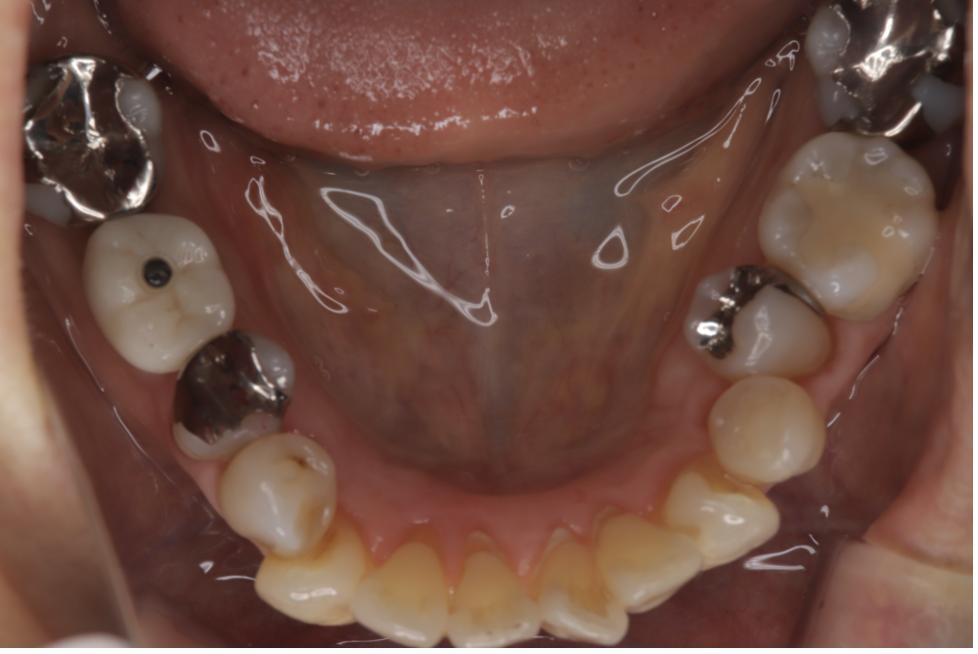

After

| 備考 | 院長より 残念ながら保存できなかった銀歯を抜歯して、インプラントを埋入しました。インプラント(人工歯根)と被せ(フルジルコニアCr)はネジで連結してあり必要に応じて外してチェックできるようになっています。写真ではメンテナンス時でネジ穴が見える状態になっています。 通常はネジ穴はプラスティックで蓋をして見えない状態になっています。 |